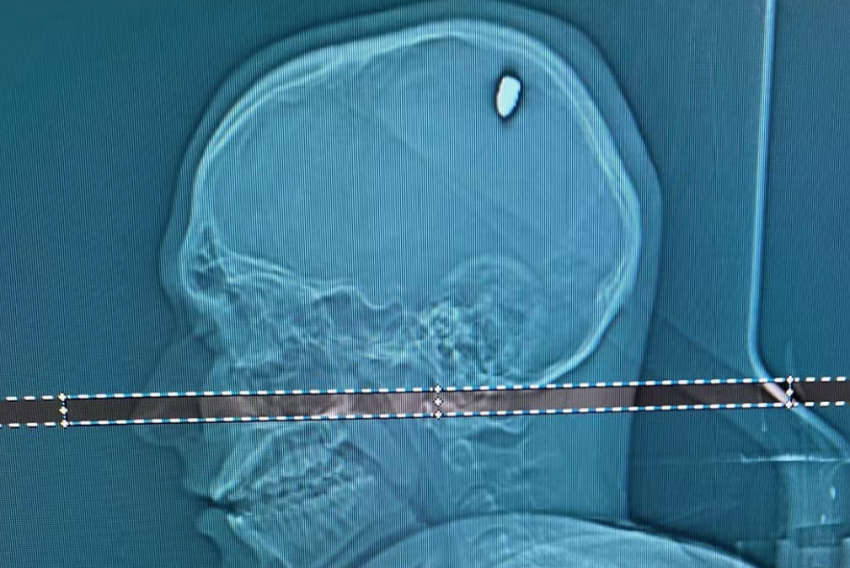

Um estudante universitário de Juiz de Fora (MG) ficou, sem saber, por quatro dias com uma bala alojada no crânio após ser atingido por um disparo em uma praia de Cabo Frio (RJ).

No dia 4 de janeiro, depois de tirar um cochilo à tarde, o estudante acordou e sentiu uma fraqueza no braço direito. Foi com a mãe para o hospital, e exames constaram que Mateus tinha uma bala na cabeça.

A bala, que entrou pela parte superior traseira da cabeça, foi retirada em cirurgia. O estudante ficou seis dias no hospital e agora está em casa.